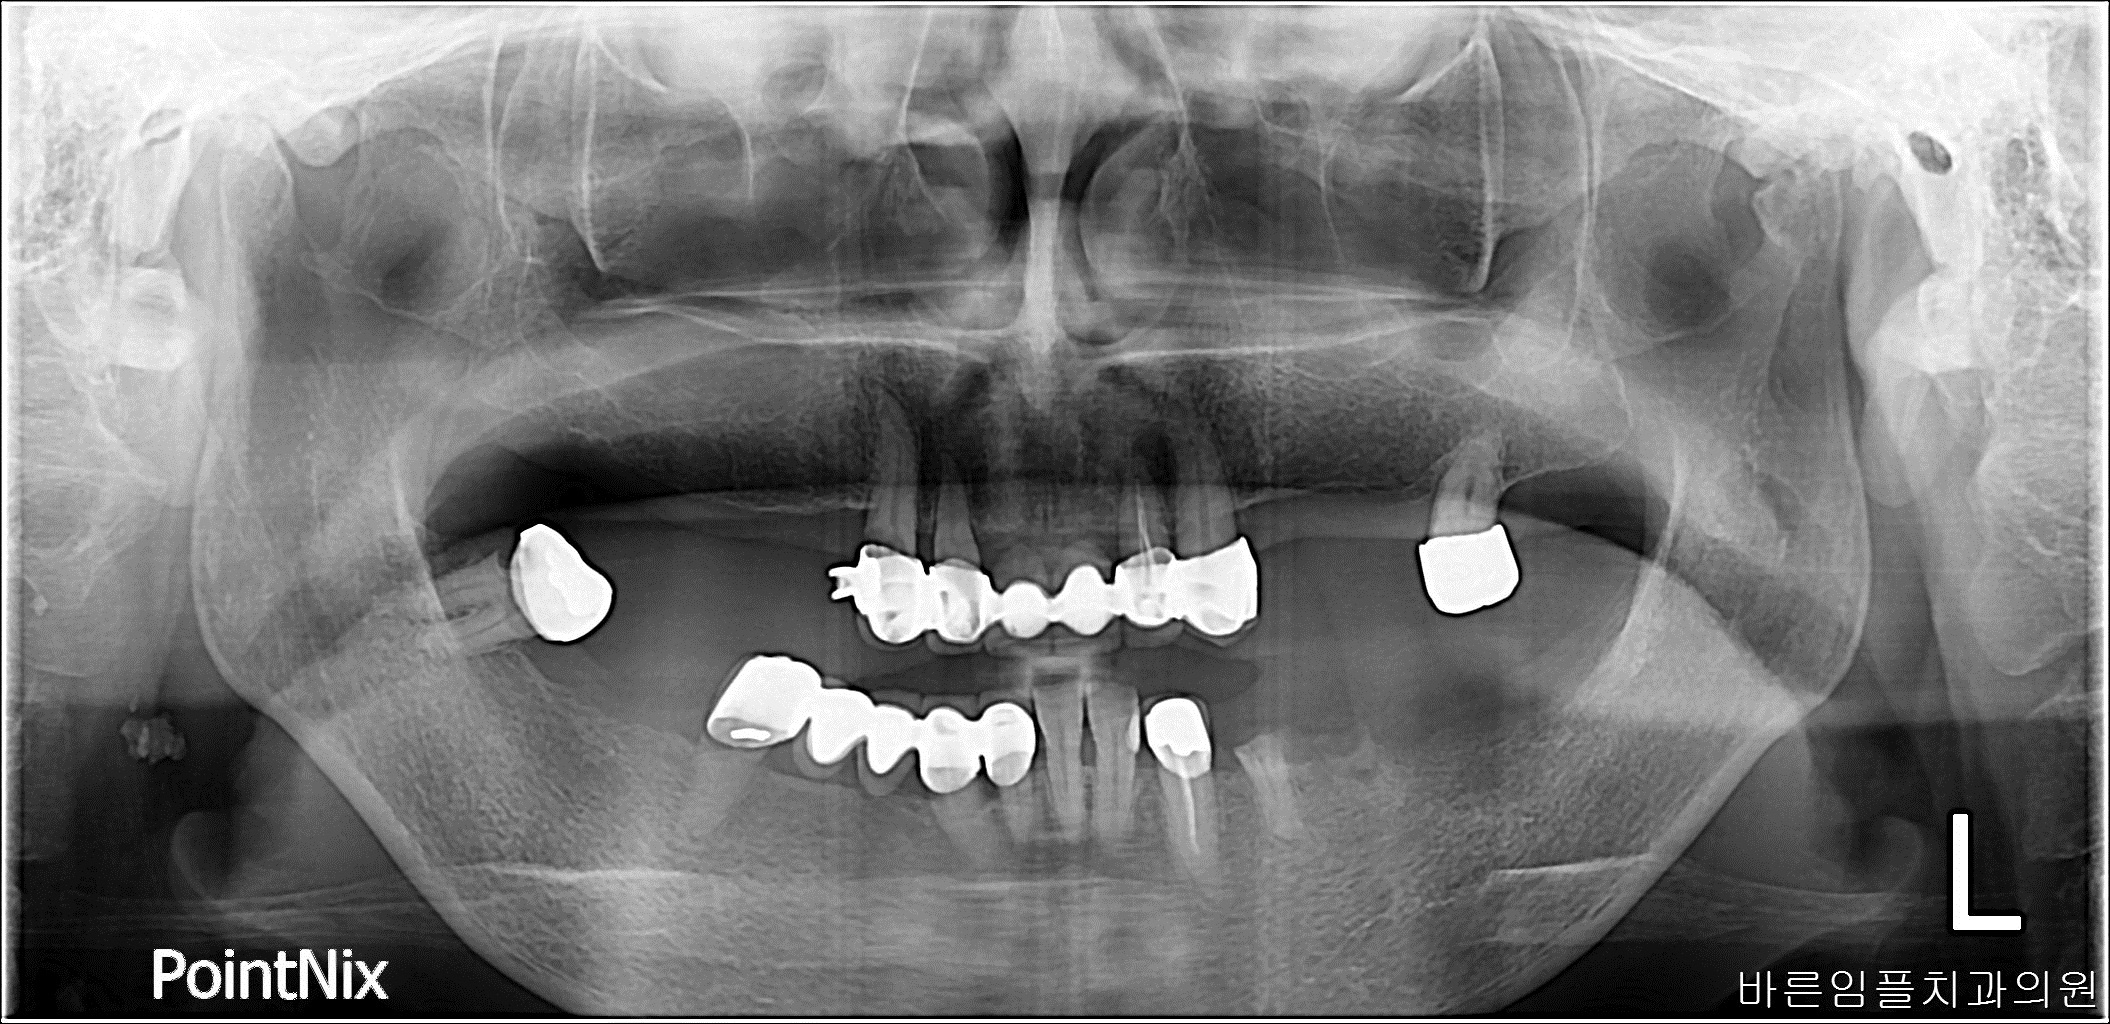

김ㅇㅇ / 수면임플란트 페이지 정보 작성일 23-10-27 16:57 2022-12-05 김ㅇㅇ Before 2023-07-04 김ㅇㅇ After 김ㅇㅇ / 수면임플란트 목록 이전글김ㅇㅇ / 임플란트 다음글 김ㅇㅇ / 임플란트